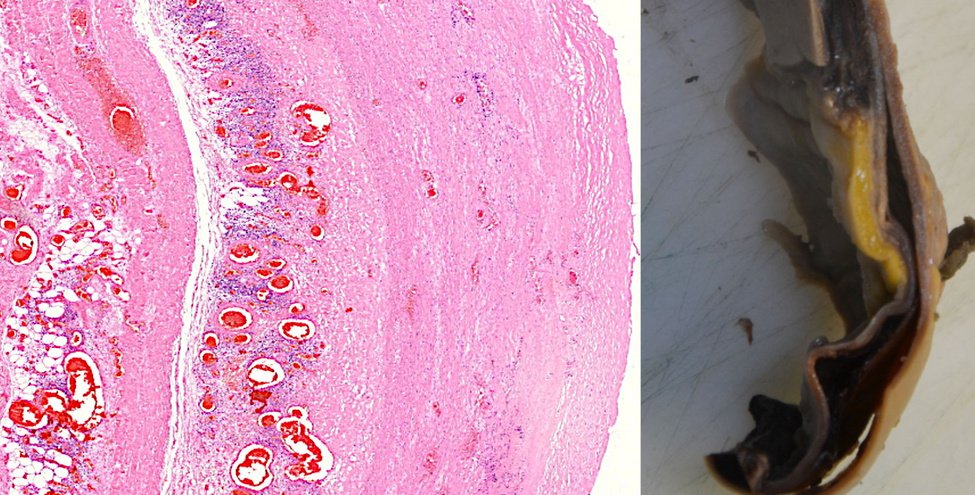

10. Una crepa nella parete dell’aorta, fiancheggiata da grappoli di linfociti, che porta alla rottura dell’aorta

A sinistra, una sezione attraverso la parete di un’aorta. Questa foto è stata scattata con un ingrandimento ancora inferiore rispetto a quella precedente; i linfociti ora appaiono solo come una nuvola di minuscoli granelli blu. A sinistra di questa nuvola blu, vediamo una crepa verticale che attraversa il tessuto. Tale crepa è anche visibile macroscopicamente nel campione asportato di un’aorta mostrato a destra.

L’aorta è il più grande vaso sanguigno del corpo. Riceve il sangue altamente pressurizzato espulso dal ventricolo sinistro del cuore ed è quindi esposto a un intenso stress meccanico. Se la parete dell’aorta è indebolita dall’infiammazione, come in questo caso, potrebbe rompersi e rompersi. La rottura aortica è normalmente piuttosto rara, ma il Prof. Burkhardt ha riscontrato più casi nel suo numero limitato di autopsie. È stato anche dimostrato che alcune delle aorte colpite esprimevano la proteina spike.